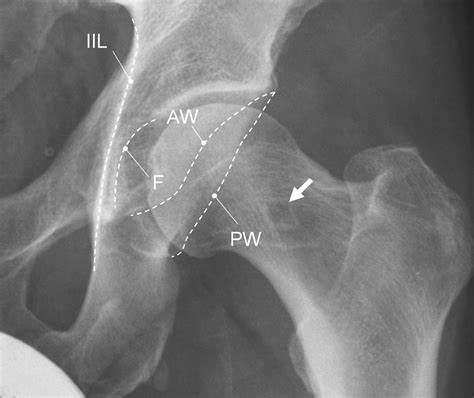

At its core, Cam Impingement Hip is a mechanical problem. A healthy hip is a "ball-and-socket" joint. The "ball" is the head of the femur (thigh bone), and the "socket" is the acetabulum (part of the pelvis). In a healthy hip, these two parts move smoothly against each other, cushioned by cartilage and the labrum—a ring of soft tissue that seals the joint.

In patients with Cam Impingement, the shape of the femoral head is not perfectly round. Instead, it has an abnormal bony growth, often referred to as a "cam" lesion. Because this bone is irregular, it cannot rotate smoothly within the socket. As you move, especially during hip flexion or internal rotation, this extra bone bumps into the rim of the socket, pinching the labrum and causing damage to the articular cartilage.

The Anatomy of FAI: A Quick Comparison

It is important to distinguish between the types of hip impingement. While Cam Impingement specifically relates to the femoral head, other types can occur either alone or in combination. The following table provides a breakdown of the differences:

Type Anatomical Issue Impact

Cam Impingement Bony bump on the femur head Causes friction against the socket rim

Pincer Impingement Excessive coverage by the socket Pinches the labrum between bone edges

Combined Impingement Mix of both Cam and Pincer Most common clinical presentation